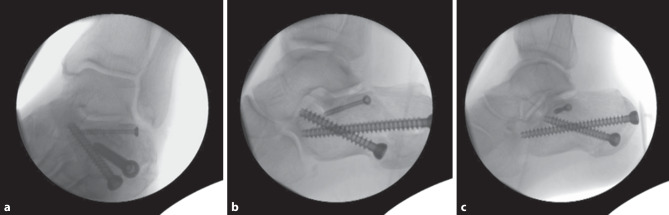

Background: Displaced intra-articular calcaneal fractures are a complication-ridden injury to treat and there are various treatment techniques to address this injury. The aim of this study was to evaluate the mid-term outcome of a percutaneous two-point distractor technique in patients with displaced intra-articular calcaneal fractures.

Methods: A retrospective data analysis of patients with intra-articular calcaneal fractures treated in a level 1 trauma center was conducted. The patients were subsequently invited for a follow-up visit to assess the mid-term outcome. The Böhler's and Gissane's angles, the American Orthopaedic Foot & Ankle Society hindfoot score, the Maryland foot score and a visual analog scale for pain were measured preoperatively and postoperatively and after at least 6 years to assess the radiological and functional outcome.

Results: Of the patients 59 completed the study with a mean follow-up of 76 months after surgery. The mean American Orthopedic Foot and Ankle Society hindfoot score at the last follow-up visit was 81, the mean Maryland foot score was 78. There were three cases (5%) of superficial wound complications and secondary arthrodesis of the subtalar joint was performed in five patients (8%).

Conclusion: The low rates of postoperative infections and secondary arthrodesis in this study underline the good to excellent mid-term functional results for a minimally invasive technique.

背景:移位的跟骨关节内骨折是一种并发症缠身的损伤治疗,有各种治疗技术来解决这种损伤。本研究的目的是评估经皮两点牵引器技术在移位的跟骨关节内骨折患者中的中期疗效。方法:回顾性分析在某一级创伤中心治疗的跟骨关节内骨折患者的资料。随后邀请患者进行随访以评估中期结果。术前、术后及至少6年后分别测量Böhler's和Gissane's角度、美国骨科足踝协会后足评分、马里兰足评分和视觉模拟疼痛量表,以评估放射学和功能预后。结果:59例患者完成研究,术后平均随访76个月。最后一次随访时,美国骨科足踝协会的平均后足评分为81分,马里兰州的平均后足评分为78分。有3例(5%)出现浅表创面并发症,5例(8%)行距下关节继发性关节融合术。结论:在本研究中,低发生率的术后感染和继发性关节融合术强调了微创技术良好到优异的中期功能效果。